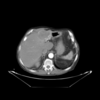

| (b) Portal venous phase (template dataset, ) | (c) Registered template, (CR-based method) | (d) Registered template, (proposed method) | |

| Figure a: Arterial phase (reference dataset, ) | |||

For the assessment of the proposed method, we carry out a comparison with the purely intensity-based variational method recently presented by the authors of this work in [26]. This CR-based approach was reported to outperform publicly available state-of-the art methods such as Elastix and ANTs in the medical setting. As can be seen in Fig.1, the proposed framework shows excellent results for the three considered registration scenarios (arterial-portal, arterial-non-contrast and portal-non-contrast), reaching average values of 1.47, 1.44 and 1.52 bits in terms of mutual information, corresponding to the arterial-portal, arterial-non-contrast and portal-non-contrast cases, respectively; this represents a mean improvement of 28.9%, 48.45% and 51.16% in relative terms of mutual information, thus outperforming the CR-based registration algorithm, which achieves a mean improvement of 26.48%, 44.22% and 43.25%, respectively. Additionally, due to the analogous behavior (i.e., comparable final values of mutual information) of the proposed method in the three scenarios, all available experiments can be grouped into one ensemble in order to assess a more comprehensive validation of the actual registration error. A ground truth was established by an expert in the form of identifiable anatomical locations (landmarks) for all experiments. The registration errors were then obtained by computing the spatial distance between the corresponding landmarks in the reference and registered template datasets. Figures Fig.2(a) and Fig.2(b) show through box plots the registration error (in millimeters) achieved by the methods under comparison, gathering the results from the three considered registration scenarios. These box plots collect the final spatial distances between corresponding landmarks, along with the median distance error and its statistical significance (notch showing the 95% confidence interval of the true median). According to Fig.2(b), the proposed method significantly improves on the registration error of the CR-based approach, since it reduces the initial median error from 9.50 mm to a residual median distance between landmarks of 1.41 mm, decreasing at the same time the outliers occurrence.

In addition to the previous measurements, the visual outcomes of two of the experiments are shown in figures Fig.3 and Fig.4, whose purpose is to highlight the most illustrative differences (from a medical point of view) between the results provided by the compared methods. In Fig.3, we observe a normal size of the liver, with discretely irregular contours and homogeneous signal intensity. In hepatic segment II, there is a lesion of 40 mm of maximum axis, encapsulated and with well-defined contours and heterogeneous enhancement in arterial phase (after administration of intravenous contrast), suggestive of hepatocellular carcinoma (HCC). In this slice of the CT scan, we can also observe the aorta that shines in the arterial phase, the lower area of the stomach and the upper area of the spleen. In Fig.4, the liver has a normal size with discretely irregular contours in relation to changes due to chronic liver disease. In hepatic segment IV, a 36 mm diameter focal lesion is identified, which has arterial phase enhancement with a small area of necrosis of 13 mm; it corresponds to a HCC previously chemoembolized with partial necrosis. In this slice of CT, we can also observe the aorta, the gastric chamber and the spleen. When comparing the two methods under study, it can be seen how in Fig.3 the resulting registered datasets are very similar. However, looking closely, it can be noticed that in the right part of the image (left side of the patient) the shape and width of the structures corresponding to the stomach and the spleen in Fig.3(d) match better those in the reference dataset. Likewise, the part of the rib at the upper right of the image is more similar to the same region in the reference dataset by using the proposed method. Regarding the experiment shown in Fig.4, it can be easily appreciated how the geometrical matching (with respect to the reference dataset, Fig.4(a)) of the structures in the right side of the image (specially the gastric chamber) is visually more satisfactory in Fig.4(d). Moreover, the area of tumor necrosis which results from the proposed method is also slightly better aligned.